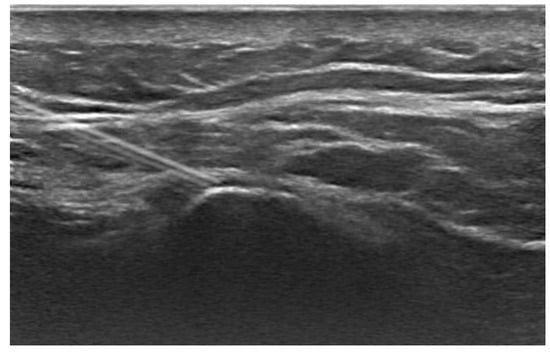

The treatment protocol adopted at the Physical and Medicine Rehabilitation Unit stipulated that each patient, after undergoing an initial assessment at baseline (T0), underwent an echo-guided infiltration (Figure 1) with lidocaine and corticosteroids at the level of the postero-superior iliac spine, and then a rehabilitative treatment of 10 sessions of 30 min each, biweekly. At the end of the first 5 weeks of treatment (T1), the patients underwent an evaluation with the clinical scales described above and a new ultrasound-guided infiltration of lidocaine and corticosteroids, followed again by a cycle of 10 rehabilitation sessions according to the scheme described above. Subsequently, patients underwent another cycle of lidocaine infiltration and corticosteroids, followed by a 10-session physical therapy program (twice a week). At the end of the second course of treatment, patients were evaluated using the rating scales described above.

Figure 1. Ultrasound-guided injection. The image shows an ultrasound-guided injection procedure with the needle precisely positioned near the spine. This technique is used to deliver medication directly to the affected area, reducing pain and improving functionality in patients with chronic low back pain.